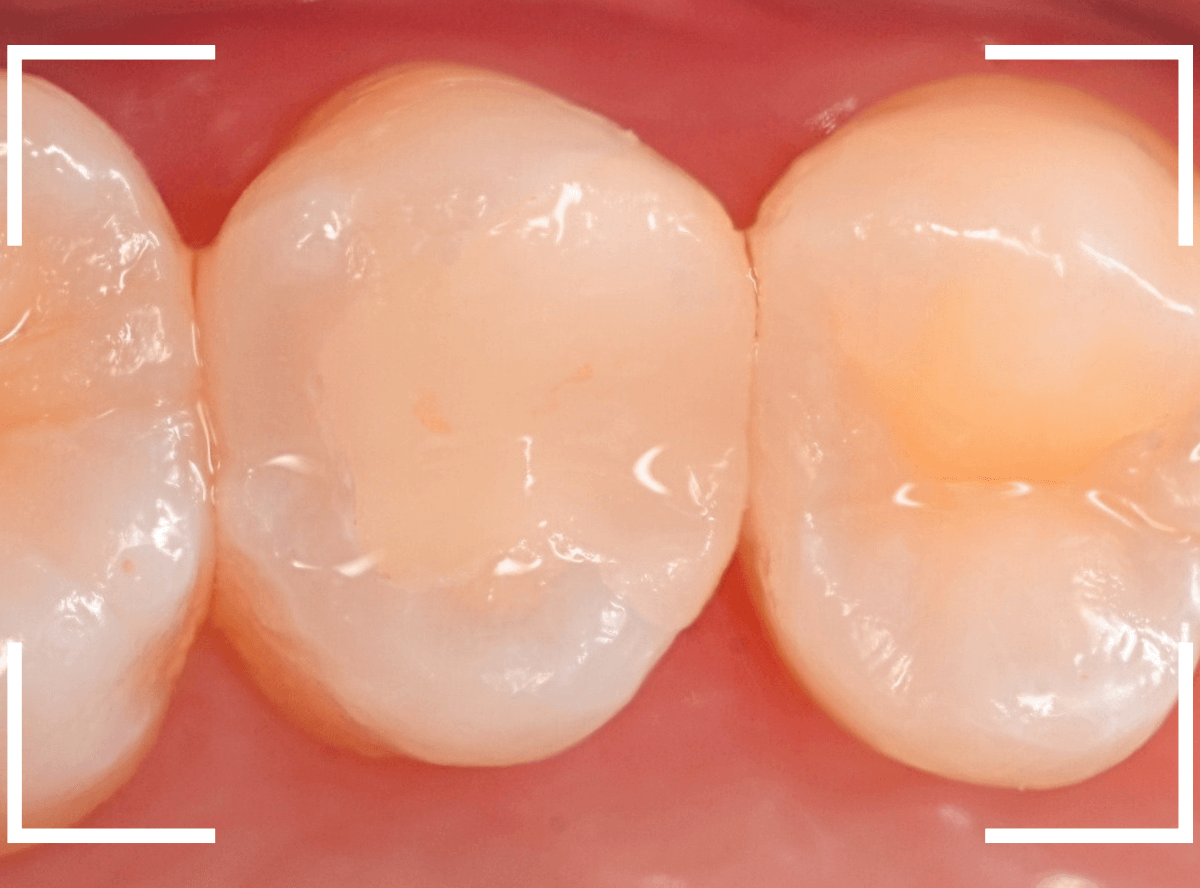

治療後の状態です。

ジルコニア・インレーはE-MAX・インレーより審美性に劣るのですが、患者さんにもご満足いただける仕上がりになり、ホッとしました。

自然な仕上がりで、患者さんにもご満足いただけました。

見た目の違和感なく、仕上げられたかと思います。

最終setした状態です。

左側の大臼歯2本が、ジルコニア・インレー

右側の小臼歯2本が、E-MAX・インレー

になります。

見た目にほとんど遜色ない仕上がりにできました。